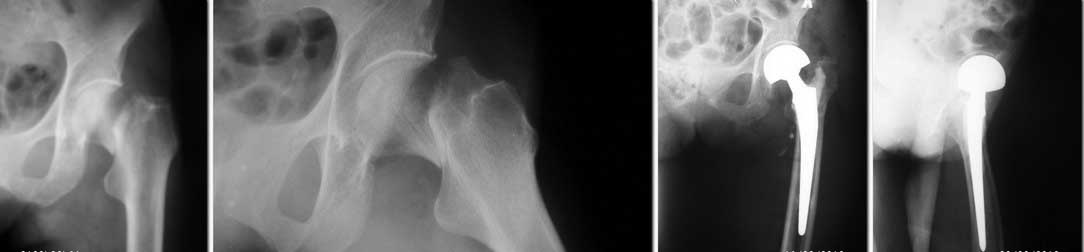

Уважаемые коллеги. Поделитесь опытом... Имеем в отделении вот такой результат эндопротезирования.

Какие рекомендации для больной в дальнейшем и чего следует ожидать при такой рентгенологической картине? Пациентке 76 лет, вес около 50 кг, операция через 5 недель после травмы.

Уважаемые коллеги, я не могу сказать, что хорошо разбираюсь в эндопротезировании суставов, но тем не менее не могу понять нескольких моментов, а именно: применялся ли цемент (судя по всему да, или мне кажется?);создается впечатление, что во время операции были некоторые сложности. Очень похоже на перипротезный перелом, но желательно выложить еще R-граммы.И по-моему немного нарушена ось ножки и соответственно ее опорные точки. Но в целом, если, коллега, это ваш дебют в эндопротезировании (и Вы стесняетесь признаться в этом), мне кажется достаточно терпимо.

Если рассматривать этот случай как salvage procedure (иначе зачем ставить биполяр?)- никаких особых "косяков" нет. Если бы это был тотальный протез - то проблем много, из тех, что очевидны - неадекватное цементирование, варусная установка ножки, низкий опил; возможно - уменьшенный офсет и вероятный импинджемент б/вертела.

Теперь к ответу. Рентенограммы точно отвратительные: разрешение плохое, где второй сустав? Поподробнее анамнез, сопутствующие, статус, пожалуйста. 76 лет, при сохранном здоровье, заслуживает тотального протеза. Вальгус ножки, невнятное цементирование и, пожалуй, все.

Создается впечатление, что цементная ножка дизайна Мюллера установлена без цемента (точнее он есть только в проксимальной части), пробки не видно, ножка ротационно и по оси не стабильна. Если это так, то думаю перспективы не радужные.